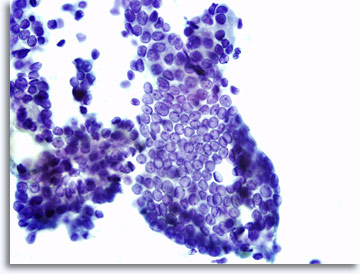

Elk willekeurig lichaamsdeel is toegankelijk voor monsterverzameling met een 22 gauge naald, inclusief minder gebruikelijke locaties zoals de hersenen, oogkas, testikels en de penis. De benadering wordt afhankelijk van het lichaamsdeel aangepast maar de techniek blijft hetzelfde. Feitelijk zal FNAB van elke willekeurige tumor materiaal opleveren, dat cellen bevat die histoarchitectuurpatronen weergeven, classificeerbaar als carcinoom, sarcoom, lymfoom, melanoom, en ongedifferentieerde maligniteit.

|

De monsterpresentatie kan licht variëren, afhankelijk van het feit of de cellen rechtstreeks op objectglaasjes zijn geplaatst of dat ze verwerkt zijn via vloeibare ThinPrep® technologie. De directe uitstrijkjes zullen achtergrondmateriaal en bloed bevatten, kernen van maligne cellen zullen gewoonlijk hyperchromatischer lijken en dens. Met ThinPrep wordt de cellulaire aggregatie gehandhaafd, terwijl achtergrondbloed wordt gelyseerd en kernen van maligne cellen minder dens en hyperchromatisch lijken. Een uitzondering kan voorkomen met de matglas vesiculatie die kenmerkend is voor papillair schildkliercarcinoom, waarin de optische veranderingen van de kernen gelijk zijn in zowel conventionele en op vloeistof gebaseerde presentaties.